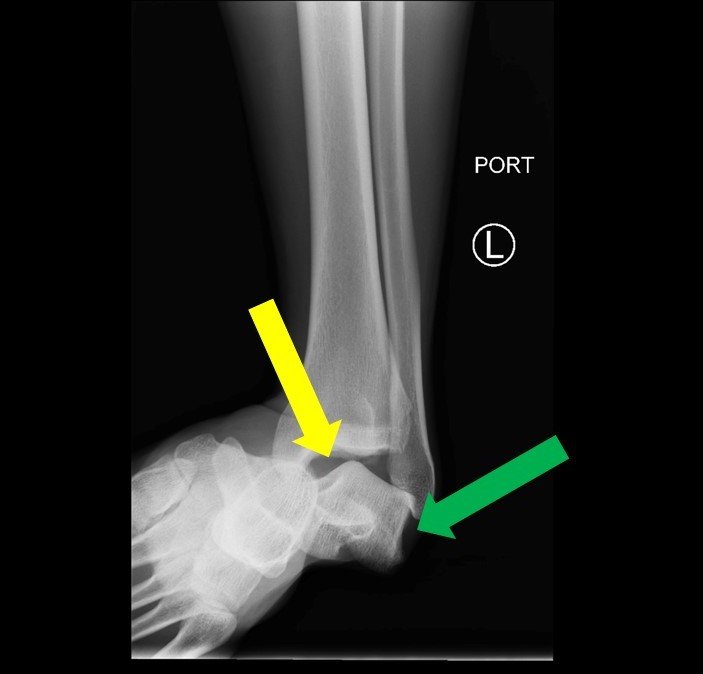

Subtalar dislocation is an unusual form of joint injury from high-energy trauma or athletic injuries. This case report describes a 22-year-old male who presented to the emergency department with left ankle pain after falling from his bicycle. Examination revealed significant deformity of the left foot and ankle. The foot pointed medially, and the bottom portions of the tibia and fibula were visible with the overlying skin intact. Radiographs confirmed left medial subtalar dislocation. There was no neurovascular compromise of the foot. The dislocation was successfully reduced under procedural sedation and the patient’s left leg was placed in a splint. He underwent post-reduction imaging and was instructed to remain non-weight-bearing and to follow up with orthopedics to discuss further management. The purpose of this report is to describe a case of a closed, medial subtalar dislocation and the approach to management.